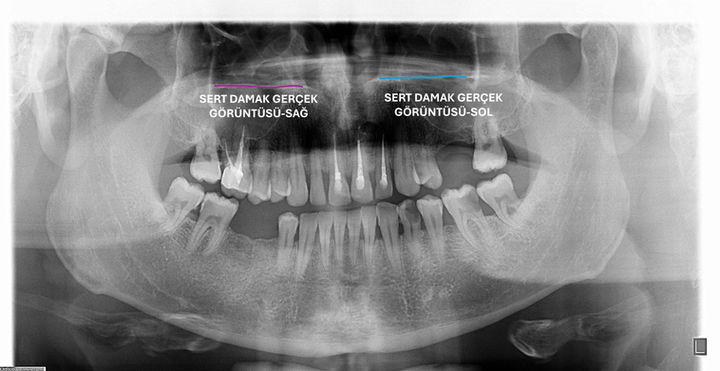

sert damak

hard palate

ghost image of hard palate